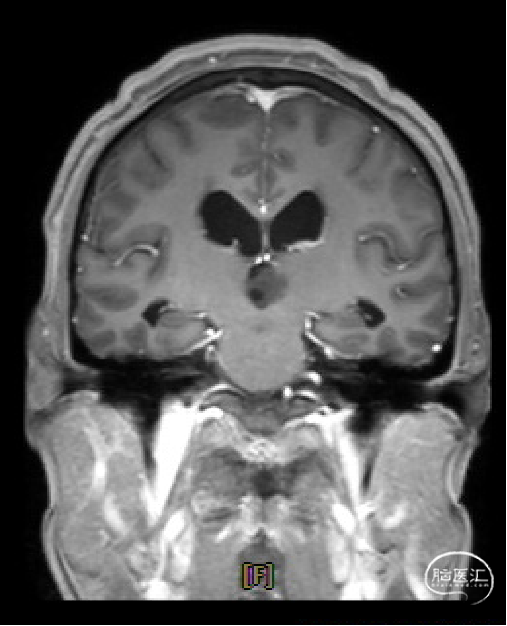

患者5年前无明显诱因出现阵发性头晕,无明显头痛、恶心呕吐等不适,开始未予重视,2022-7-19出现头晕加重,伴视力下降,遂于2022-7-24在当地医院行颅脑MRI提示:松果体区肿瘤伴梗阻性脑积水。

双眼粗测视力下降,眼球向上活动受限。

初步诊断

松果体区占位,胶质瘤?生殖细胞肿瘤?

脑积水